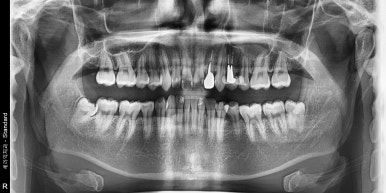

임플란트 수술 전 이미 치아가 발치되어 있는 상태

2023-01-06

치과에 오시는 환자분들 중에는 이미 치아가 발치 되어있는 환자분들도 꽤 계신데요.

다른 치과에서 발치를 하신 경우도 있고, 잇몸 상태가 너무 좋지 않아서 저절로 치아가 빠진 경우도 있습니다.

치주염이 악화되어 잇몸뼈가 소실된 나머지 치아를 계속 지탱하고 있을 수 없어 치아가 빠져버리는 것이죠.

예를 들어 만약 환자분이 오늘, 2024년 1월 18일에 저희 치과에 오셔서 엑스레이를 찍으셨다고 가정해볼게요.

엑스레이에서 임플란트 해야할 치아가 있었던 것이 확인이 되는 경우에는

추후 발치 후 임플란트를 식립한다면 아마 보장받으시는데 큰 문제는 없으실 겁니다.

치아가 상실된 상태에서 내원해주신 케이스

2023-03-03

하지만 만약 임플란트 해야하는 치아가 엑스레이 상에서 확인이 되지 않는다면 문제가 될 수 있어요.

다른 치과에 해당 치아를 발치했다는 기록이 있고, 엑스레이로도 확인이 가능한 경우라면 괜찮지만

자연적으로 빠진 경우에는 보장개시일 이후 치아가 있었다는 것이 증명되지 않으니

임플란트치아보험 지급을 거절할 수도 있습니다.